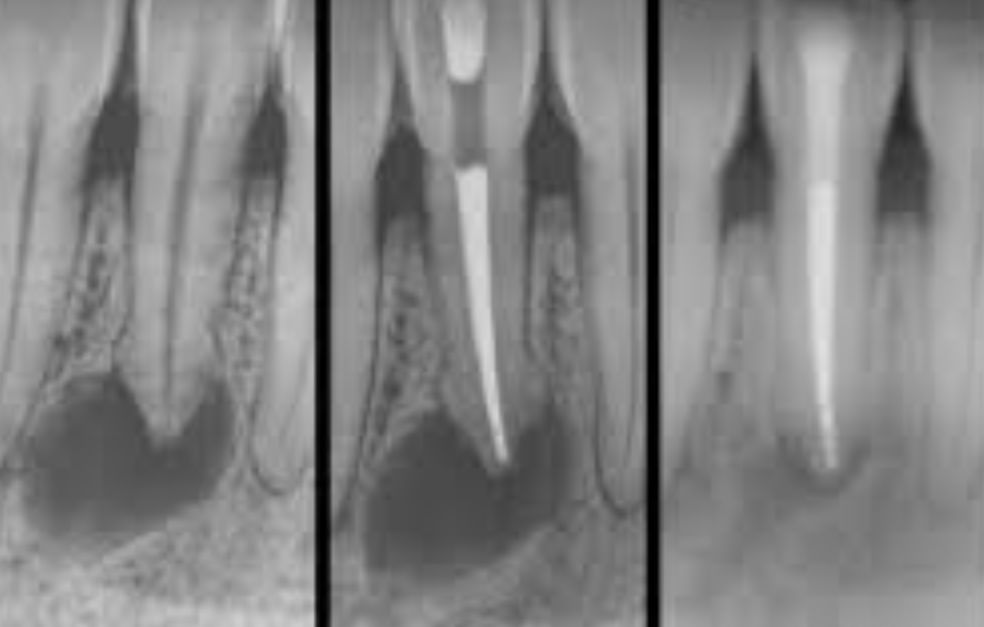

Examen radiographique

- Début : image radioclaire faible en « croissant de lune » au tiers apical

- Extension : image arrondie ou ovalaire, contours diffus, centre radioclaire, effacement de la trabéculation osseuse

- Persistance : destruction radiculaire (aspect « sucé »), destruction centrifuge de l’os alvéolaire

3.3 Thérapeutique du Granulome Péri-apical

Traitement endodontique classique (traitement de choix)

- Triade : parage + désinfection + obturation canalaire

- Le succès dépend de l’élimination complète du contenu canalaire et d’un scellement apical correct

- Surveillance clinique : risque de réaction péri-apicale aiguë dans les jours suivant l’obturation — prescription d’antalgiques préventifs, drainage si suppuration

- Surveillance radiologique : trimestrielle, puis à 6-12 mois → disparition de l’image radioclaire, reconstitution de la trame alvéolaire